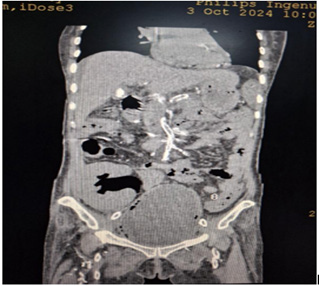

Cystoscopy was done to detect mucosa lesions in bladder; the whole mucosa was congested and red. There were multiple hemorrhagic areas in whole bladder mucosa; it was bled on touch. There was no focal ulcer or tumor. Therefore, generalized congested mucosa, hemorrhagic areas were probably due to DIC or CMV cystitis or candida cystitis or bacteria cystitis. The color of urine coming from Vescio-ureteric orifice of graft kidney was clear. Hemostasis was done with Ball electrode; bladder wash out was done with Tomey’s glass syringe. Figure 9-15 reveal cystoscopy findings. Abdominal tomogram was done; it revealed a swollen allograft kidney with air in the renal pelvis and renal vessels and subcapsular area suggestive of emphysematous allograft pyelonephritis. And, air along bladder wall was seen indicating emphysematous cystitis. They are illustrated in (Figure 16-19).

Figure 16: CT abdomen axial view non-contrast showing swollen allograft kidney with air in the renal pelvic.

Figure 17: CT abdomen coronal view non-contrast showing swollen allograft kidney with air in the renal pelvic, subcapsular area and air along bladder wall.

Figure 18: CT abdomen coronal view non-contrast showing swollen allograft kidney with air in the renal pelvic, subcapsular area and air in the bladder.